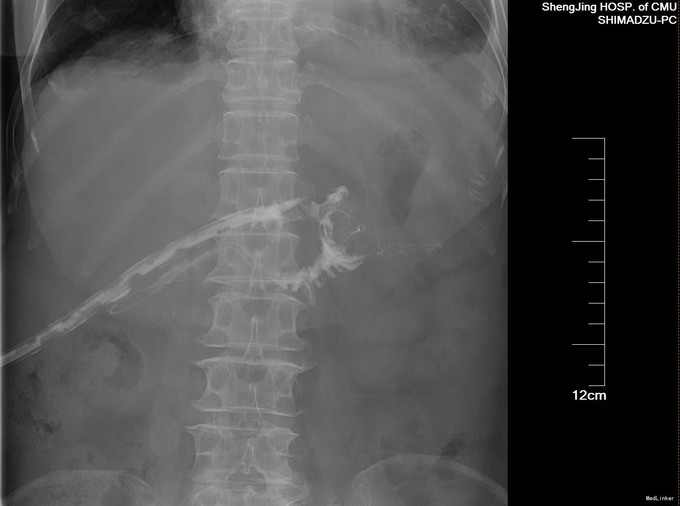

术后复查CT, 胰肠吻合口周围渗出较多,肠壁水肿,肝内胆管多发气体密度影。双侧胸腔可见液性密度影,双肺下叶膨胀不良。术后动态监测引流液淀粉酶,前5天不高,术后7天引流液淀粉酶超过1万,按照2005年国际胰瘘定义研究小组( international study group on pancreatic fistula , ISGPF) 对胰瘘的定义:术后≥3 d 起从手术放置的引流管(或以后放置的引流管或经皮穿刺引流) 中引出淀粉酶大于正常血清淀粉酶水平3 倍的液体且引流量可计,本例属于胰瘘。胰瘘既可以是胰肠吻合口瘘,也可以是来源于胰腺实质的与吻合口无关的渗漏,进一步经引流管造影,发现肠粘膜显影,提示胰肠吻合口瘘。胰瘘分为无临床症状的A级胰瘘,临床相关的B级胰瘘,导致病人腹痛、发热或血中性粒细胞升高,需要使用抗生素、全胃肠外营养(TPN)或生长抑素等治疗,还有威胁生命的C级胰瘘,需要积极使用抗生素、TPN或生长抑素,甚至需要手术或转入重症监护病房,也可能术后死亡,本病例属于最轻的A级胰瘘。胰腺术后总体胰瘘发生率20-40%,胰体尾切除后胰瘘发生率高于胰头切除术后。本例虽发生胰瘘,但是症状轻,最终术后3周愈合,拔管出院。